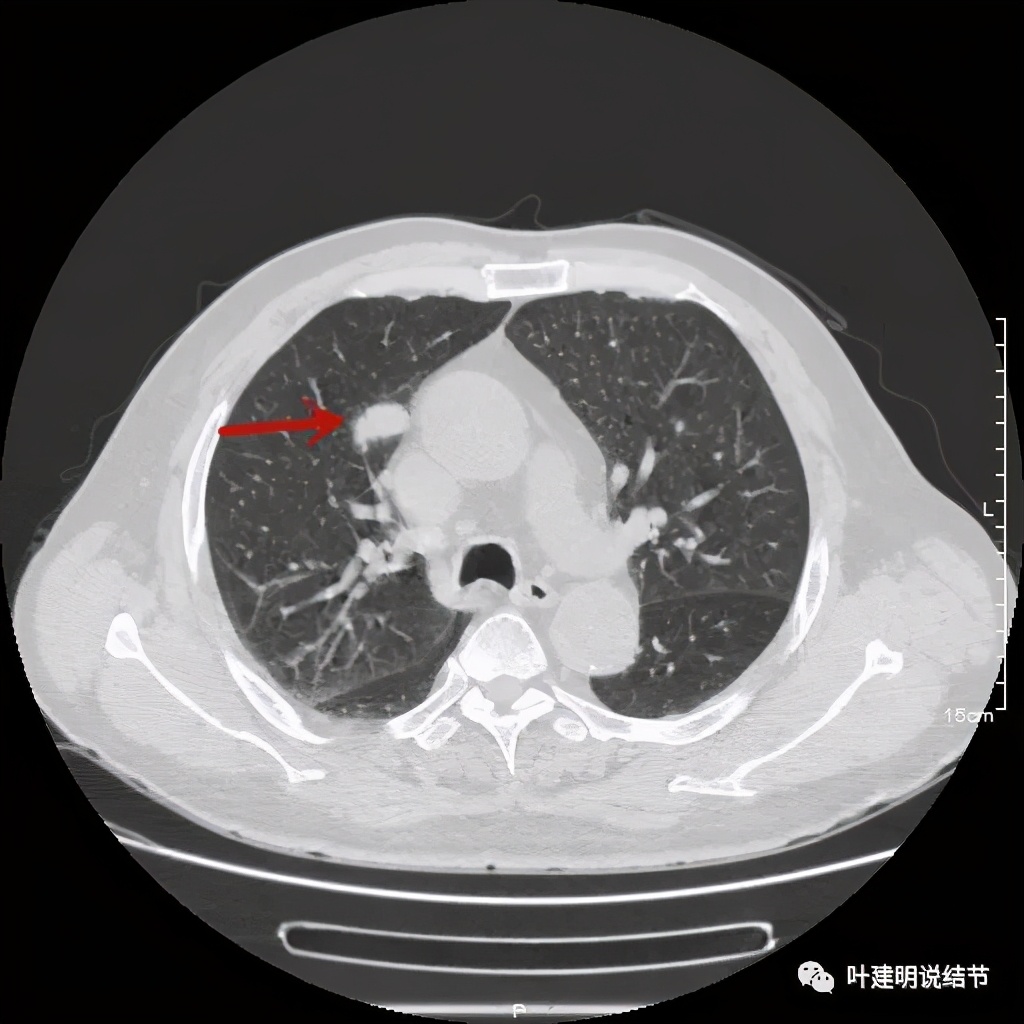

上图也示病灶密度不均,但边缘过于光滑(绿色);支气管似有截断(粉色);局部有点状钙化(蓝色)

病灶在上图层面似见支气管也是贴壁的。那么增强后又是如何呢?

上图示病灶边缘过于光滑(绿色);局部有点状钙化(蓝色)